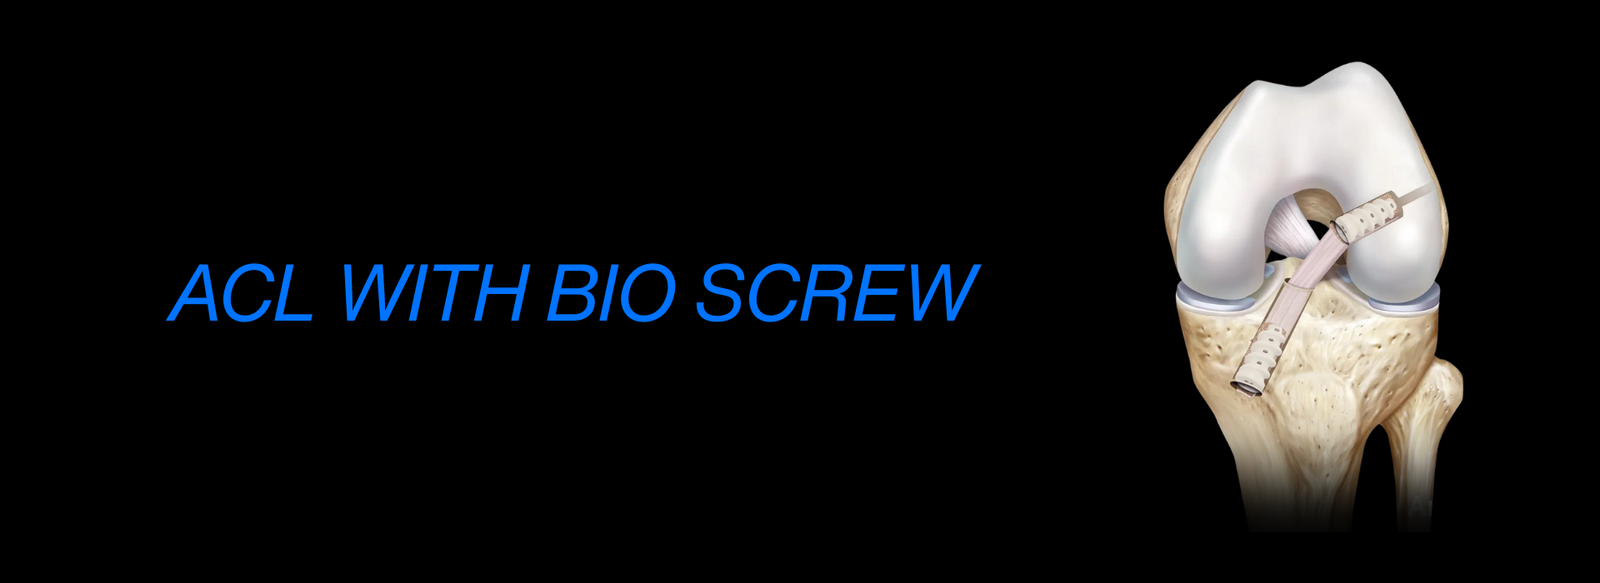

Fellowship in Arthroscopy: Expertise in minimally invasive surgery to diagnose and treat joint conditions, such as torn cartilage or ligament injuries, particularly of the knee, shoulder, and hip.

AO Recon Hip & Knee Arthroplasty: Advanced training in reconstructive surgeries, particularly hip and knee replacements, for patients suffering from degenerative diseases or complex injuries.